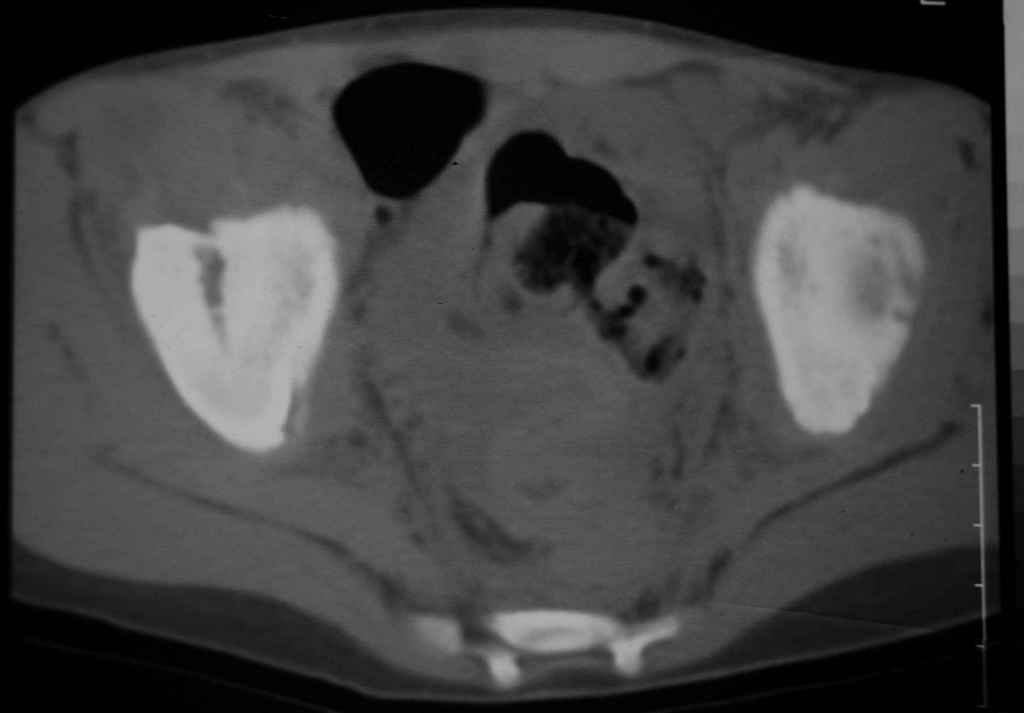

Уважаемые коллеги, помогите определиться с тактикой лечения. Ребёнок 7 лет, травма

11.09.08, поступил с травматическим вывихом бедренной кости. Вывих вправлен, конечность

фиксирована на скелетном вытяжении. Что делать с переломом подвздошной кости? Лечить

консерватино или оперировать?